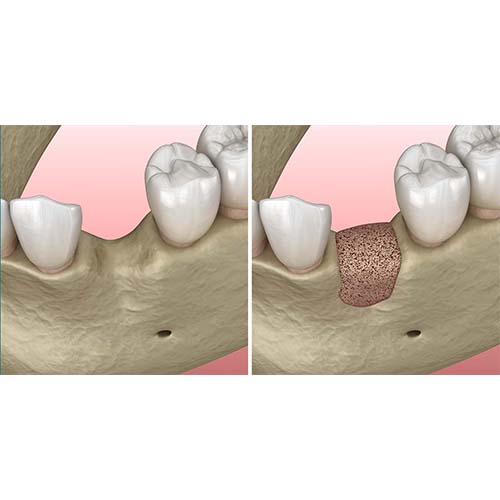

インプラント治療をする際に、骨が足りずにインプラントを埋入できない場合に行う骨造成手術の術式の一つです。

インプラントは上顎洞(上あごの奥歯の部分の骨の中にある空洞)の下にある骨に埋め込みますが、歯が抜けてしまって時間が経っている場合や歯周病などが原因となり骨が少なくなり、インプラントを埋入できないケースがあります。

サイナスリフトは非常に高い技術が必要となるため、すべての歯科医院で実施できるわけではありません。当院では、院長が多数の症例を経験しており、難症例でも対応が可能です。骨の厚みが足りなくてインプラントができないといわれたことがある方は是非一度当院へご相談ください。